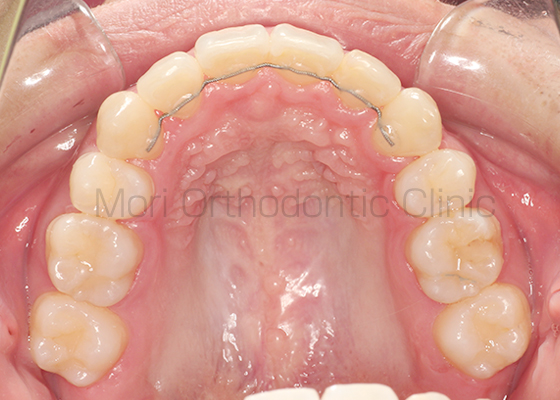

術前

術後

| 主訴 | 出っ歯、歯並びが悪い |

|---|---|

| 診断名 | AngleⅠ級叢生 |

| 年齢 | 21歳11か月 |

| 治療装置 | Multi-Bracket(フルリンガル) |

| 抜歯部位 | 14,24,34,44 |

| 治療期間 | 2年7か月 |

| 治療費 | 1,180,200円(税込) |

| リスク・副作用 | 矯正治療による歯の移動に伴う痛み、歯根吸収、歯肉退縮、虫歯 |